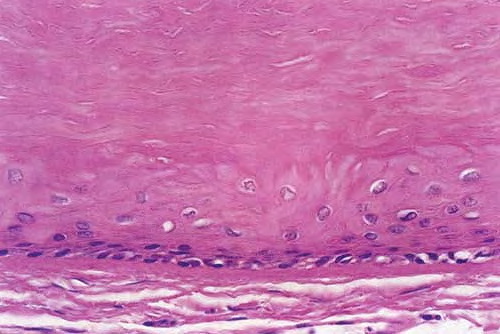

Trichilemmal cyst = كيسة غمد الشعرة